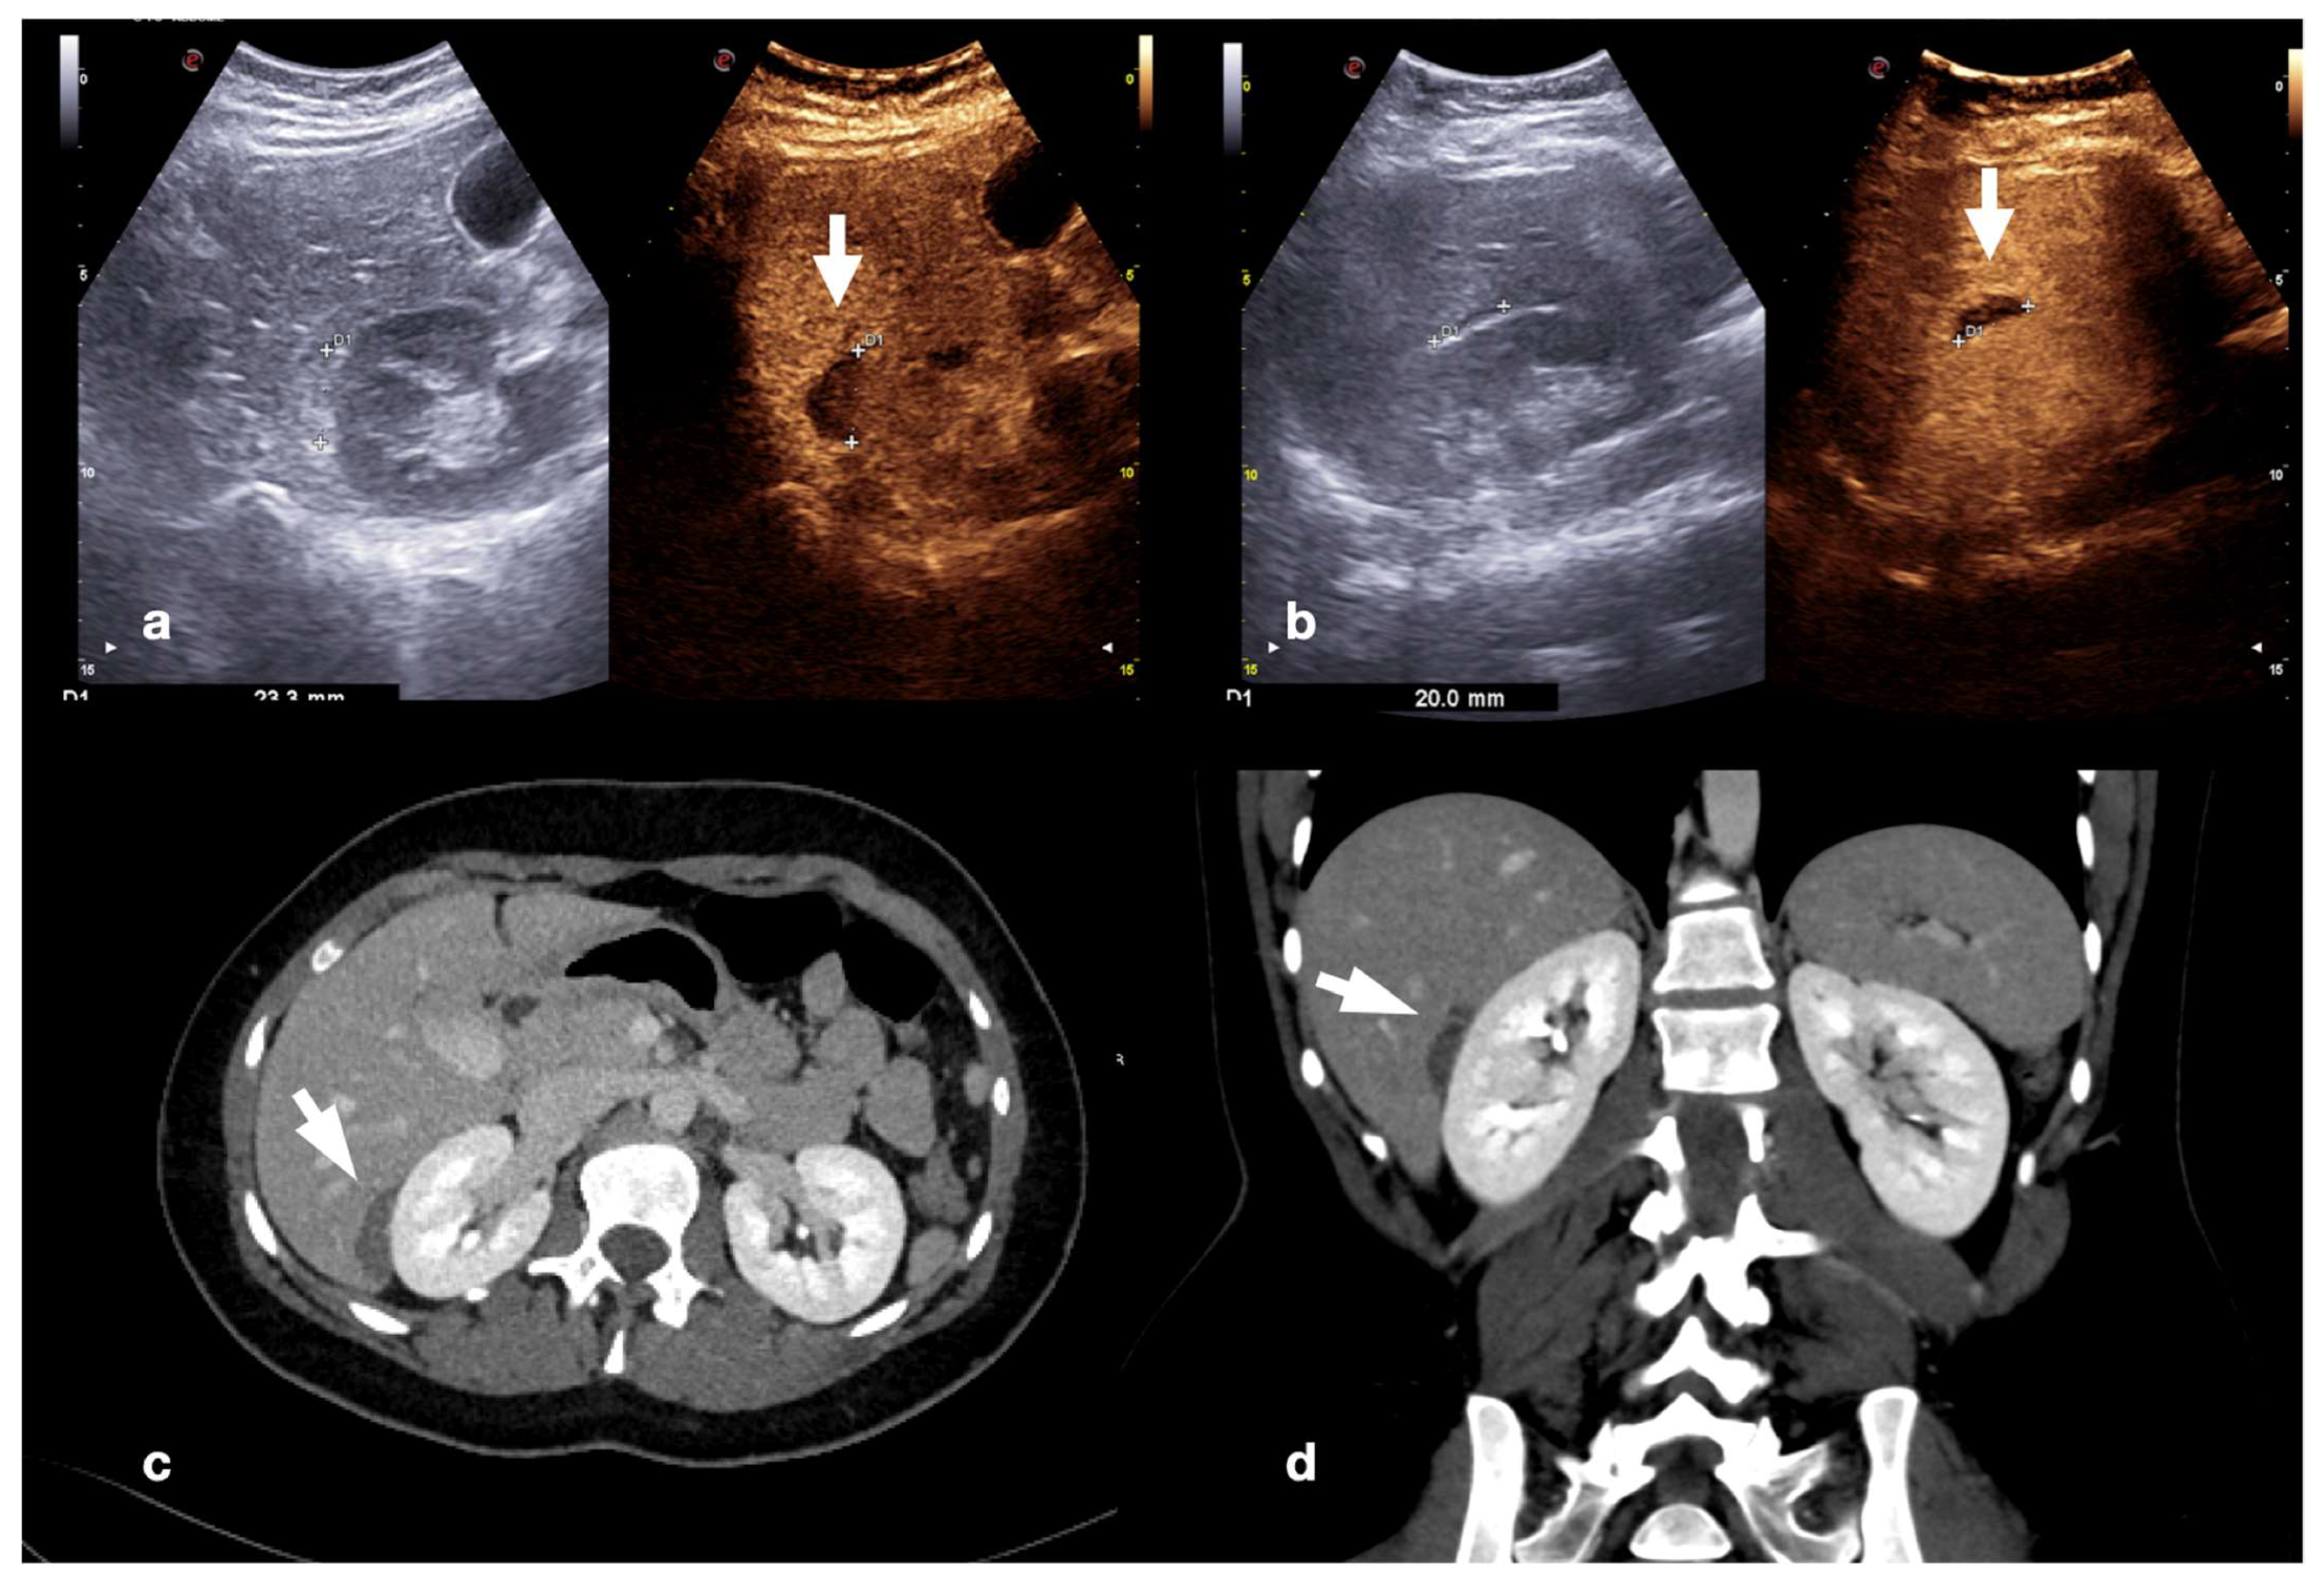

Contained vascular injuries include pseudoaneurysms and arteriovenous fistulas. Pseudoaneurysms are focal outpouchings of the external vessel contour due to the partial disruption of the wall, which is contained by the tissue around the vessel (Figure 18, Figure 19 and Figure 20) [1,30].

Figure 18.

Admission CT (a) and follow-up CEUS (b) of the spleen of the same patient as Figure 14. At admission CT, in the arterial phase, was noticed a small hilar pseudoaneurysm (a, arrow). CEUS was performed after the embolization, showing the lack of vascular enhancement in the pseudoaneurysm site (b, arrow). Adopted from ref. [30], 2021, Iacobellis, F.; et al.

Figure 19.

High grade traumatic splenic injury with vascular complication. Arterial (a) and venous (b) phase CEUS examination in a 25−year-old patient admitted at the emergency department for blunt abdominal trauma, showing multiple splenic lacerations and a voluminous arteriovenous fistula (white arrowhead). Subsequent arterial (c) and portal vein (d) phase contrast-enhanced CT scan further confirmed the diagnosis (black arrowhead).

Figure 20.

CEUS (a) of a 23−year-old man referring to the emergency department for direct blunt trauma to the right flank showed the presence of a small pseudoaneurysm (white arrow) inside the contusion area of the right kidney; the diagnosis was then confirmed at the axial arterial phase contrast-enhanced CT scan (b), as well as at angiography performed for treatment purposes (c).

Arteriovenous fistulas consist of traumatic communication between the arterial and venous systems [1,30]. Fistulas are characterized as asymmetrical, early contrast opacification of a vein during the early arterial phase of the study (Figure 21).

Figure 21.

Companion case of Figure 2b. Renal arteriovenous fistula (white arrowhead) at color–Doppler US (a) and CEUS (b), confirmed (c) at contrast-enhanced CT scan (arterial phase, coronal MIP reconstruction) and subsequent angiography (d).